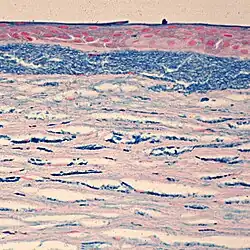

Die makuläre Hornhautdystrophie (MCD) ist eine sehr seltene und schwere angeborene Form einer Hornhautdystrophie mit parenchymatöser knötchenförmiger Hornhauttrübung beidseits mit wolkigen Schleierbildungen.[1][2]

Klinische Kriterien sind:[2][1]

- Beginn meist im ersten Lebensjahrzehnt

- anfangs Schleier, später über die gesamte Hornhaut verteilte Flecken und Knötchen

- ausgeprägte Sehminderung, mit dem Alter zunehmend